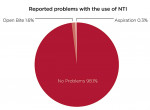

Four hundred and fourteen providers responded to a question about future use of the nociceptive trigeminal inhibition splint for pain management. They were queried about whether they planned to continue using the NTI for pain management at the same rate as in recent years, or planned to increase or decrease its use. Thirty-two percent (n = 133) stated they would increase their use for this indication (Figure 6). Approximately 97% stated they would maintain (n = 268) or increase (n = 133) their levels of NTI use. Of 511 responses to a question regarding fabrication techniques, 34% (n = 172) exclusively use direct fabrication, 31% (n = 160) use the laboratory-fabricated method, and 35% (n = 179) use both methods. The number of patients reported to have developed a clinical observation of an anterior open bite subsequent to use of the device was reported as 1.6% of 78,711 cases (Figure 7). Of patients reporting aspiration of the device (0.3%), no events were documented by radiograph or other means.

This is the first published study of a large group of dentists using an anterior nociceptive trigeminal inhibitory splint in clinical practice. The survey sample of 587 was composed mostly of general dentists with 5 or more years’ experience using the device. The majority of respondents reported using the device for both the treatment of OFP and for the protection of teeth and restorations. Just over one quarter of the sample (26%) use the device primarily for pain management. A large number of respondents (87%) reported using the device for both short- and long-term treatment. Of those respondents (n = 36) using the device for short-term use only, just over half of them (n = 19) indicated they restricted treatment time to avoid possible changes in occlusion. One common concern often expressed by dentists about the use of a device that only covers anterior teeth is that an anterior open bite might result. Yet in this survey, the incidence of anterior open bite subsequent to the use of the device (based on 512 responses) was 1.6%. Previous reports on adverse events are limited by a small sample.34 This study, the largest to date, provides substantial provider-based evidence of the NTI’s clinical benefit and minimal occurrence of adverse events. Many dental providers base their overall opinion on the NTI splint on a perception of adverse events. This study helps to clarify the prevalence of these events. Further investigations of its efficacy and possibly related adverse events through randomized clinical trials with large patient populations and clearly defined criteria are needed.